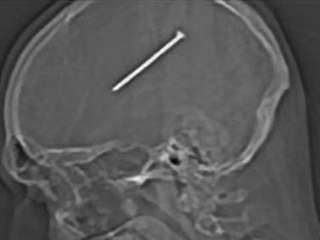

Il passe à quelques centimètres de la mort